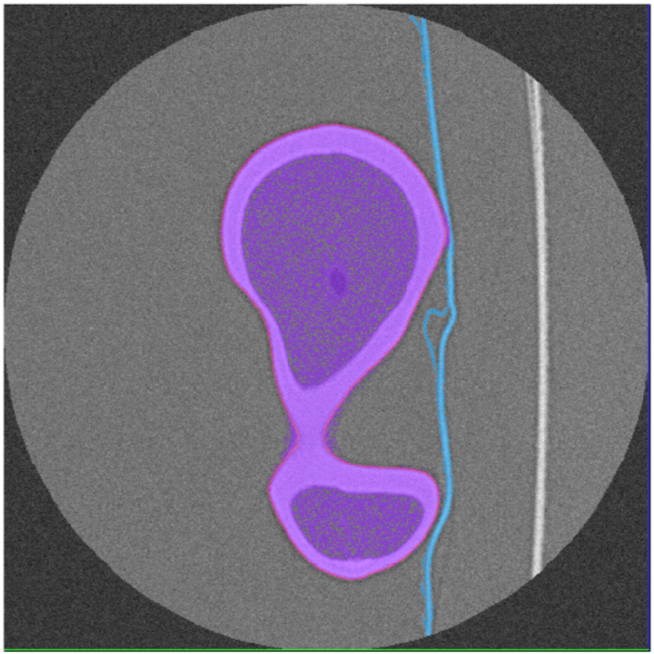

Two outputs may be produced after segmentation refinement (Fig. 2), a high-resolution point cloud model obtained directly from the interpolated image, and a down-scaled version of the high-resolution segmentation. The surface mesh model obtained from the point cloud will be referred as Point Cloud (PC) model. Since image refinement is performed independently in each image, the PC model is produce directly from a set of equally spaced contours by tiling the cloud points. The surface mesh of the down-scaled version was generated in Simpleware ScanIPTM v4.0𝑣4.0v4.0, with standard pre-smoothing and mesh refinement settings [49][50], and will be referred simply as ScanIP Mesh (SM) model. The segmentation pipeline was tested in noise-free and noisy images, corrupted with AWGN with a standard deviation of σNoise=10subscript𝜎𝑁𝑜𝑖𝑠𝑒10\sigma_{Noise}=10 HU. Fig. 5 shows the sub-stpng of the segmentation refinement process when applied to both noise-free and noisy images. The Hausdorff Distance (HD) and the Mean Symmetric Distance (MSD) [51] were applied to evaluate each segmentation outcome.

Figure 5: Segmentation refinement pipeline applied to the Dataset #1: in (a) the original image data without noise; in (b) the image data after de-noising with anisotropic diffusion and image deconvolution; in (c) image cropping and interpolation around the pre-segmented region; and in panel (d) the final segmentation contour superimposed over the pre-segmentation mask; in (e), (f), (g) and (h) image refinement is applied to the same image corrupted with AWGN

Fig. 6 shows the final PC model obtained from the segmentation of Dataset #1 and the comparison with the Nikon Metris LK𝐿𝐾LK V20𝑉20V20 gold standard, whereas Fig. 7 depicts the down-scaled segmentation within Simpleware ScanIPTM v4.0𝑣4.0v4.0 overlapped with reference surface. A close agreement between both PC and SM, and the gold standard is observed for both models. The agreement between the PC and SM model and the gold standard for all noise-free and noisy Datasets regarding the distance measures are summarized in Table II and Table III, respectively.

Figure 7: On left (a) the domain pre-segmentation and final segmentation after refinement for the Dataset #1, in the middle (b) the surface mesh generated with Simpleware ScanIPTM and the reference model, and the comparison between the two models (c)